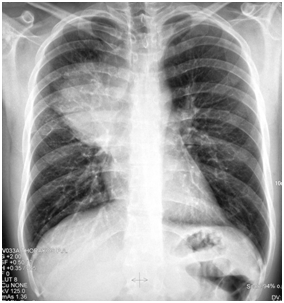

The 1st case we report is of a 22-year-old Caucasian male, who was admitted to our hospital with a 3-days history of progressive dyspnea on exertion, neck swelling, fatigue, persistent chest pain, pyrexia, and a cough that was occasionally productive of blood. The physical examination revealed a heart rate of 115 beats per minute (Sinus Rhythm), a respiratory rate of 25 breaths per minute and superficial vascular distention over the neck. Laboratory studies revealed elevated serum α-fetoprotein (AFP) (5380 IU/ml) and D-dimer (481ng/ml). A chest X-ray in the poster - anterior view, upon admission, depicted a suggestive right upper mediastinal mass (Bild 1). Radiography was followed by contrast-enhanced CT scan that revealed a large, homogeneous mediastinal mass crossing into the anterior mediastinum and compressing – encasing the superior vena cava. It also showed signs of thrombosis of the left brachiocephalic vein, and multiple filling defects at the left pulmonary artery indicating embolism. Subcarinal lymphadenopathy, as well as enlarged lymph nodes of the right hilum was present (Bild’s 2-5). On median sternotomy, a large non resectable tumor was observed involving the in nominate vein and the superior vena cava (Bild 6). Great care was taken to remove as much tumor mass as possible. To decompress the superior vena cava, we had to perform an extensive resection and reconstruction of the cephalad part of the superior vena cava using homolog pericardium.A histopathological examination of a section of the mass revealed a mixed NSGCT (embryonal yolk sac/endodermal sinus tumour), containing also elements of embryonal carcinoma (Figure 1-6).The patient was placed on cisplatin-based chemotherapy (BEP regimen: cisplatin 50mg/m2 on days 1-2, etoposide 165mg/m2 on days 1-3, bleomycin 30U on days 1, 8, and 15, every 3 weeks). Tumor markers were elevated for a-FP (214ng/mL) and normal for β-HCG. The patient completed 4 cycles of chemotherapy and the subsequent chest CT (Bild 7) revealed a partial remission of the mass (decrease>50% of the size). The a-FP was normal as well as the β-HCG. The remaining mass was inoperable so the patient was started on salvage chemotherapy with the TIP (paclitaxel, ifosfamide, ciplatin) regimen for 4 cycles. The post-chemo chest CT showed stable disease and the patient was referred to radiation oncologists for radiotherapy of the remaining tumor. Three months later af P was found elevated and the CTs revealed multiple brain metastases. Whole brain radiation was performed and the patient was placed on gemcitabine (d1 and d8 every 21 days). Two months later the neurologic status deteriorated with new brain metastases and the patient passed away (19 months after the diagnosis).

Bild 1 Yolk sac tumor. The initial chest radiograph demonstrating soft tissue fullness along the right hilum and mediastinum that obscures the hilar anatomy.